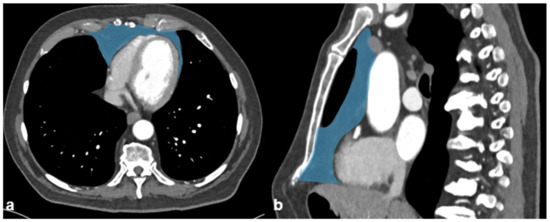

Sarcopenia was semiautomatically assessed by CT-based parameters measured at the level of the fifth thoracic vertebra by excluding fatty-infiltration using a CT-attenuation threshold of −29 to 150 Hounsfield units (HU). According to the literature [23], sarcopenia was defined as less than the sex-matched 33rd percentile of the respective muscle area: cross-sectional total paraspinal area (TPA), total rotator-cuff area (TRA), and total pectoral area (TPeA). Total muscle area (TMA) was defined as the sum of the former three measurements (Figure 1).

Figure 1. Morphometric measurements cross-sectional total paraspinal area (TPA, green), total rotator-cuff area (TRA, red), and total pectoral area (TPeA, yellow). Total muscle area (TMA) was defined as the sum of the former three measurements segmented on axial cross-sectional plane at the level of the fifth thoracic vertebra. Both transverse processes are visible in this plane.